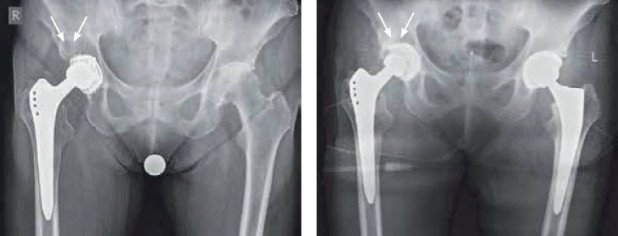

Präoperative Situation mit einer schmerzhaften Arthrose in der linken Hüfte und einer grossen Knochenzyste über der noch stabilen Pfanne rechts (Abb. 3). Es wurde eine Hüftprothese links implantiert. In gleicher Narkose wurde mit dem links entnommenen Femurkopf der grosse Knochen defekt rechts gefüllt und ein neues Polyethylen-Inlay in günstigerer Position in die Pfanne zementiert (Abb. 4).